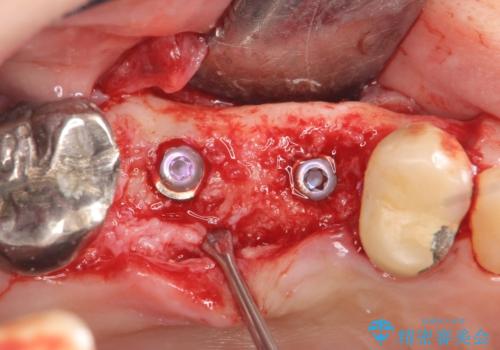

右上の567ブリッジを外したところ、右上5は歯根破折により保存不可能だったため、右上56部にインプラントを埋入し欠損補綴を行いました。

また右上5部に関しては抜歯時に歯槽堤保存術(抜歯窩に人工骨の填入を行う手術)を行い、骨の欠損を最小限に止めています。